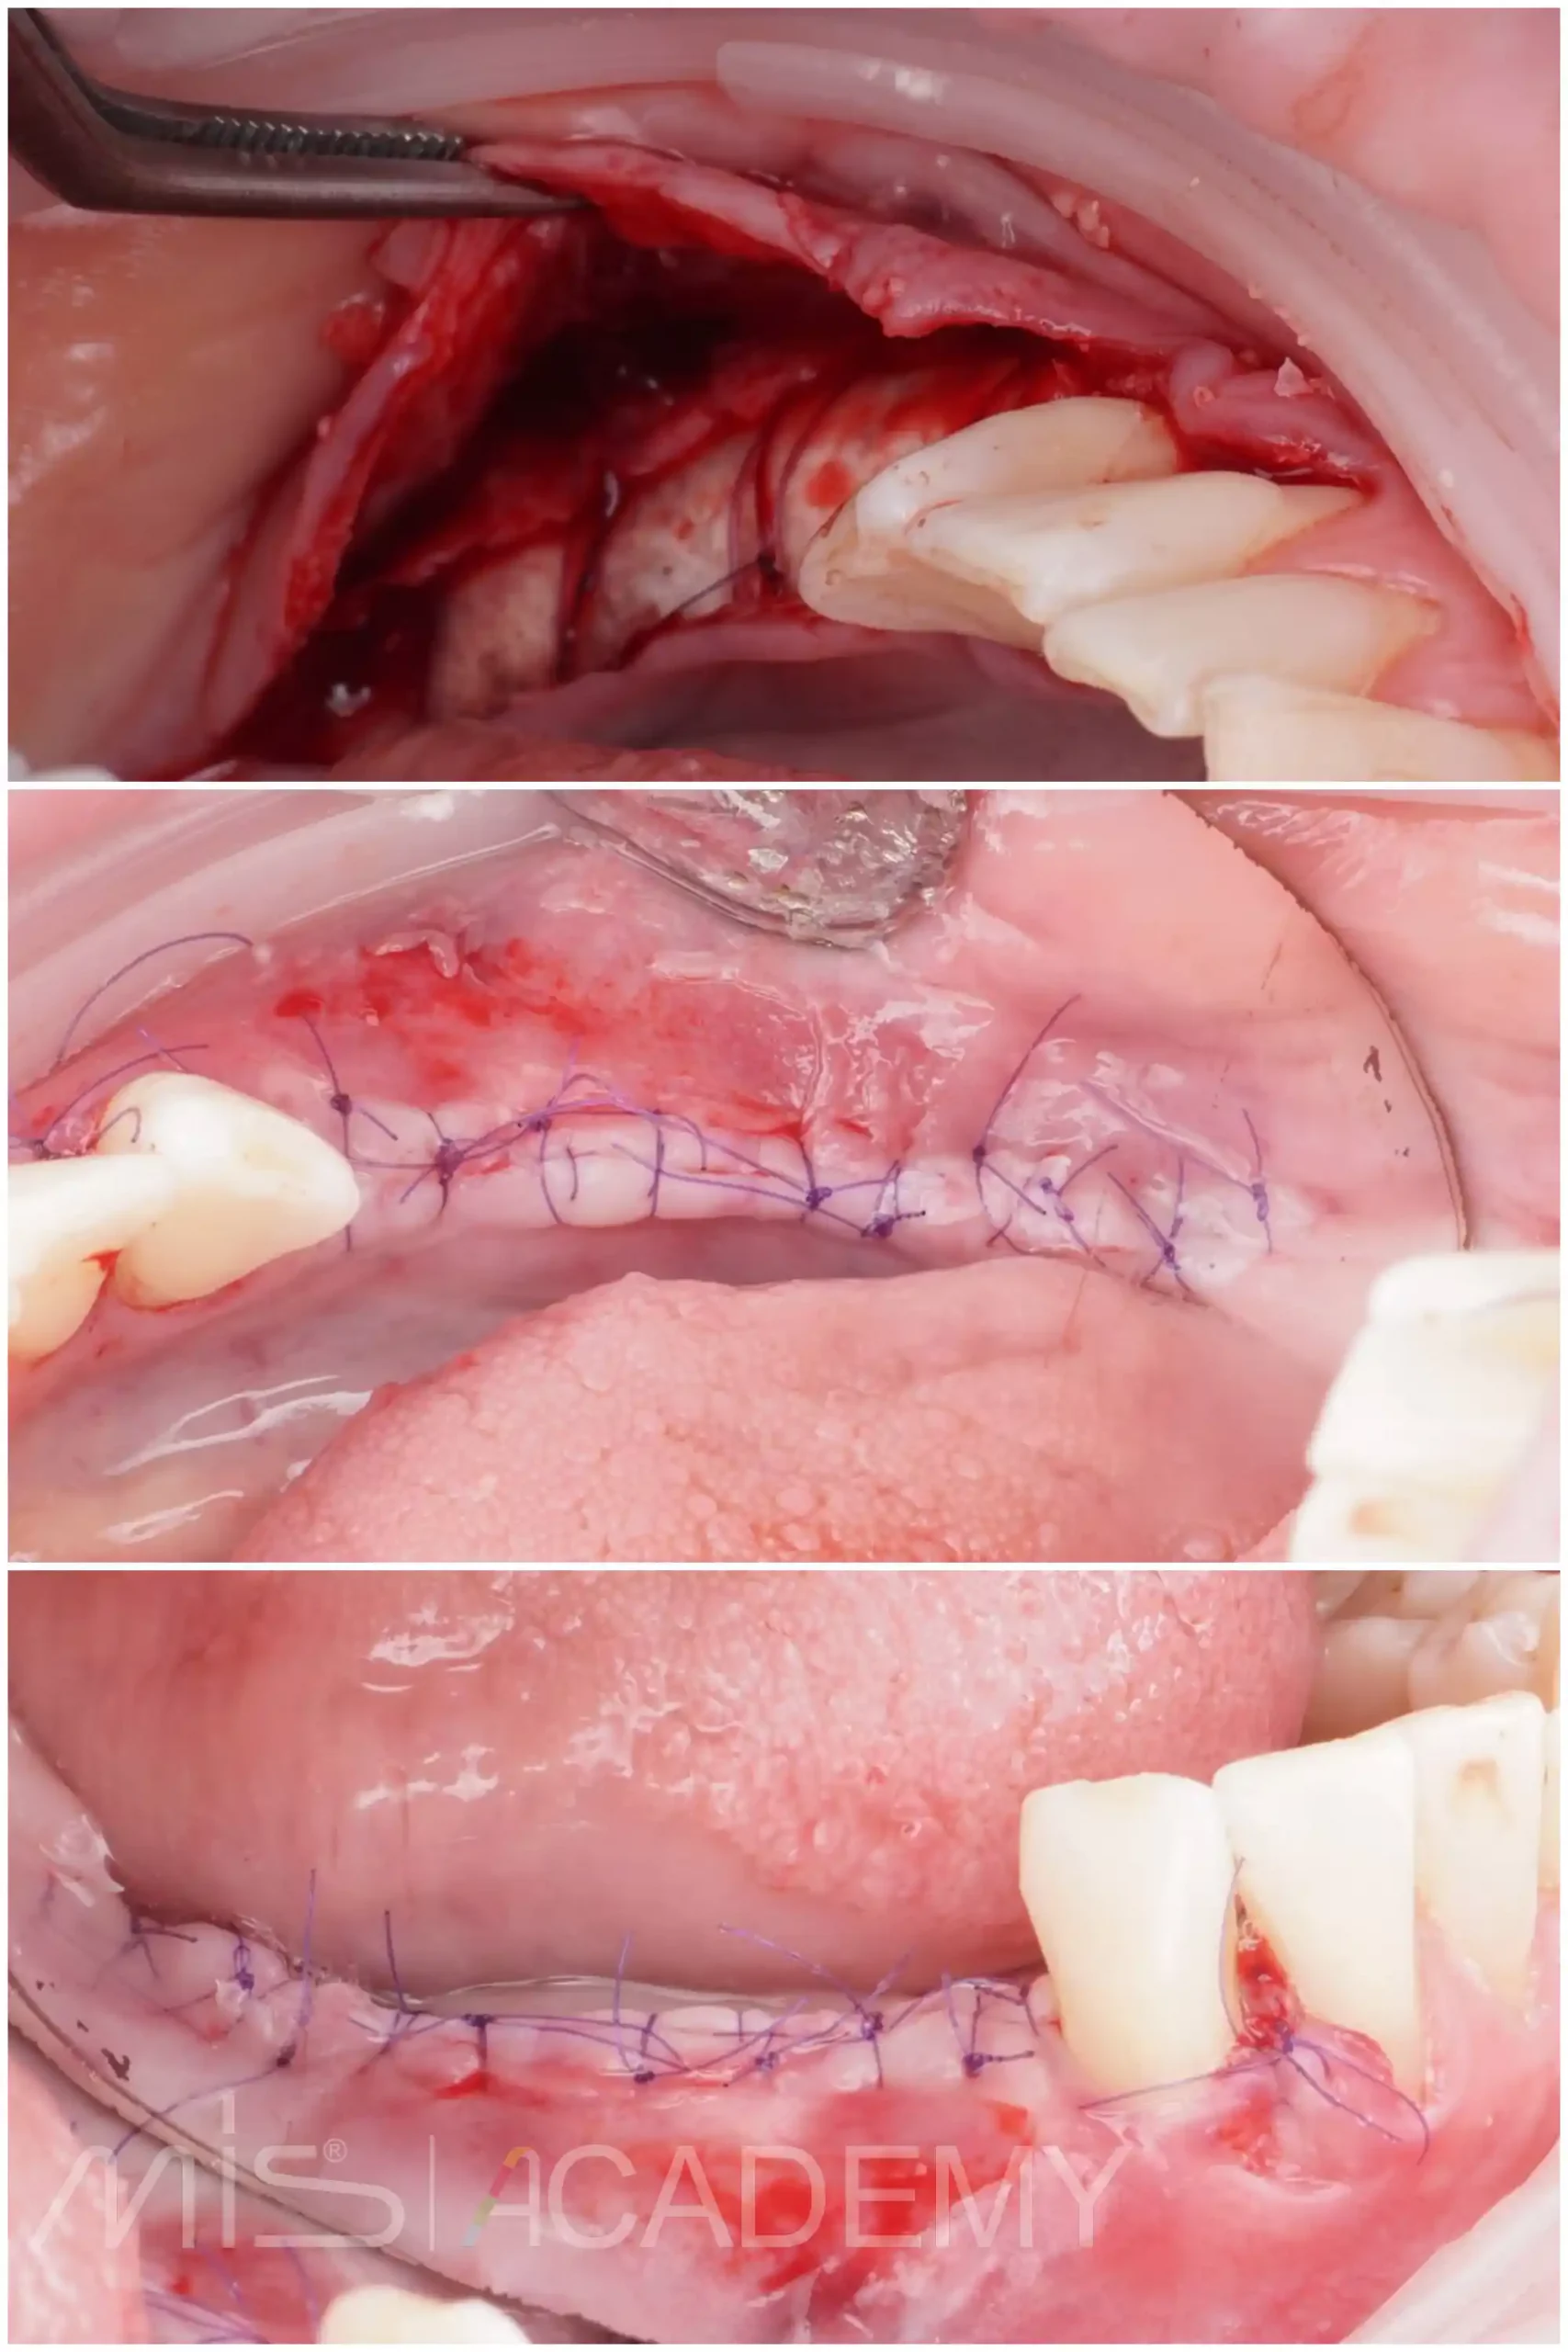

— Раскрытие через 6 месяцев. Ламина до конца не резорбировалась, аккуратно без проблем удаляем, под ней был миллиметровый фиброз, под которым плотный фундамент. Фиброз не удаляю, чуть отодвигаю в зоне где будет имплантация, дою дозреть и использую его для фиксации ССТ с бугра.